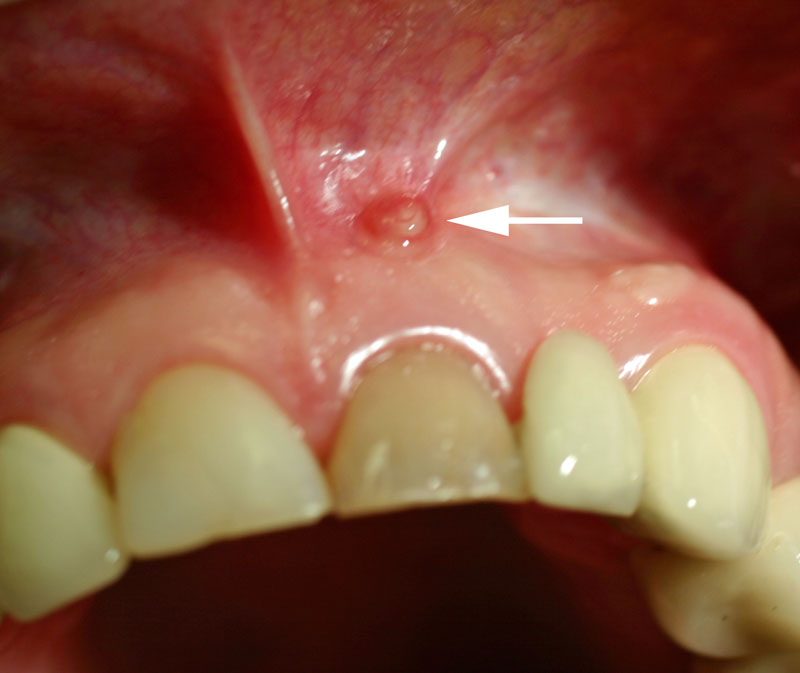

آبسه دهان

در صورت رعایت نکردن و ایجاد عفونت در لثه، ممکن است به تشکیل ورم چرکی در دهان، که آبسه نامیده میشود بیانجامد. آبسه به درمان سریع نیاز دارد. شخصی که آبسه دارد، ممکن است ورم دردناک و ترشح چرک از لثه داشته باشد. عفونتهای درمان نشده، عوارضی به همراه دارد؛ برای مثال:

بافت عفونی ممکن است ریشه دندان کناریاش را در وضعیت خطرناکی قرار دهد که در نهایت این امکان وجود دارد که آن دندان از بین برود.

علاوه بر آن، عفونت بافت ممکن است به فک یا استخوان اطراف منتقل شود و باعث آسیب به بافت شود. باکتری همچنین ممکن است وارد جریان خون شود و در سایر قسمتهای بدن مشکلی ایجاد کند.